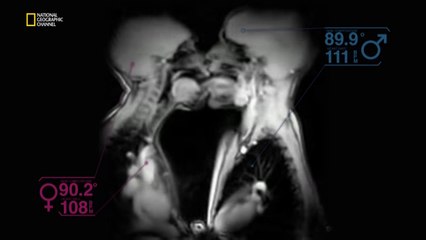

KalPenn ile Büyük Resim - Nasıl Yayılıyor